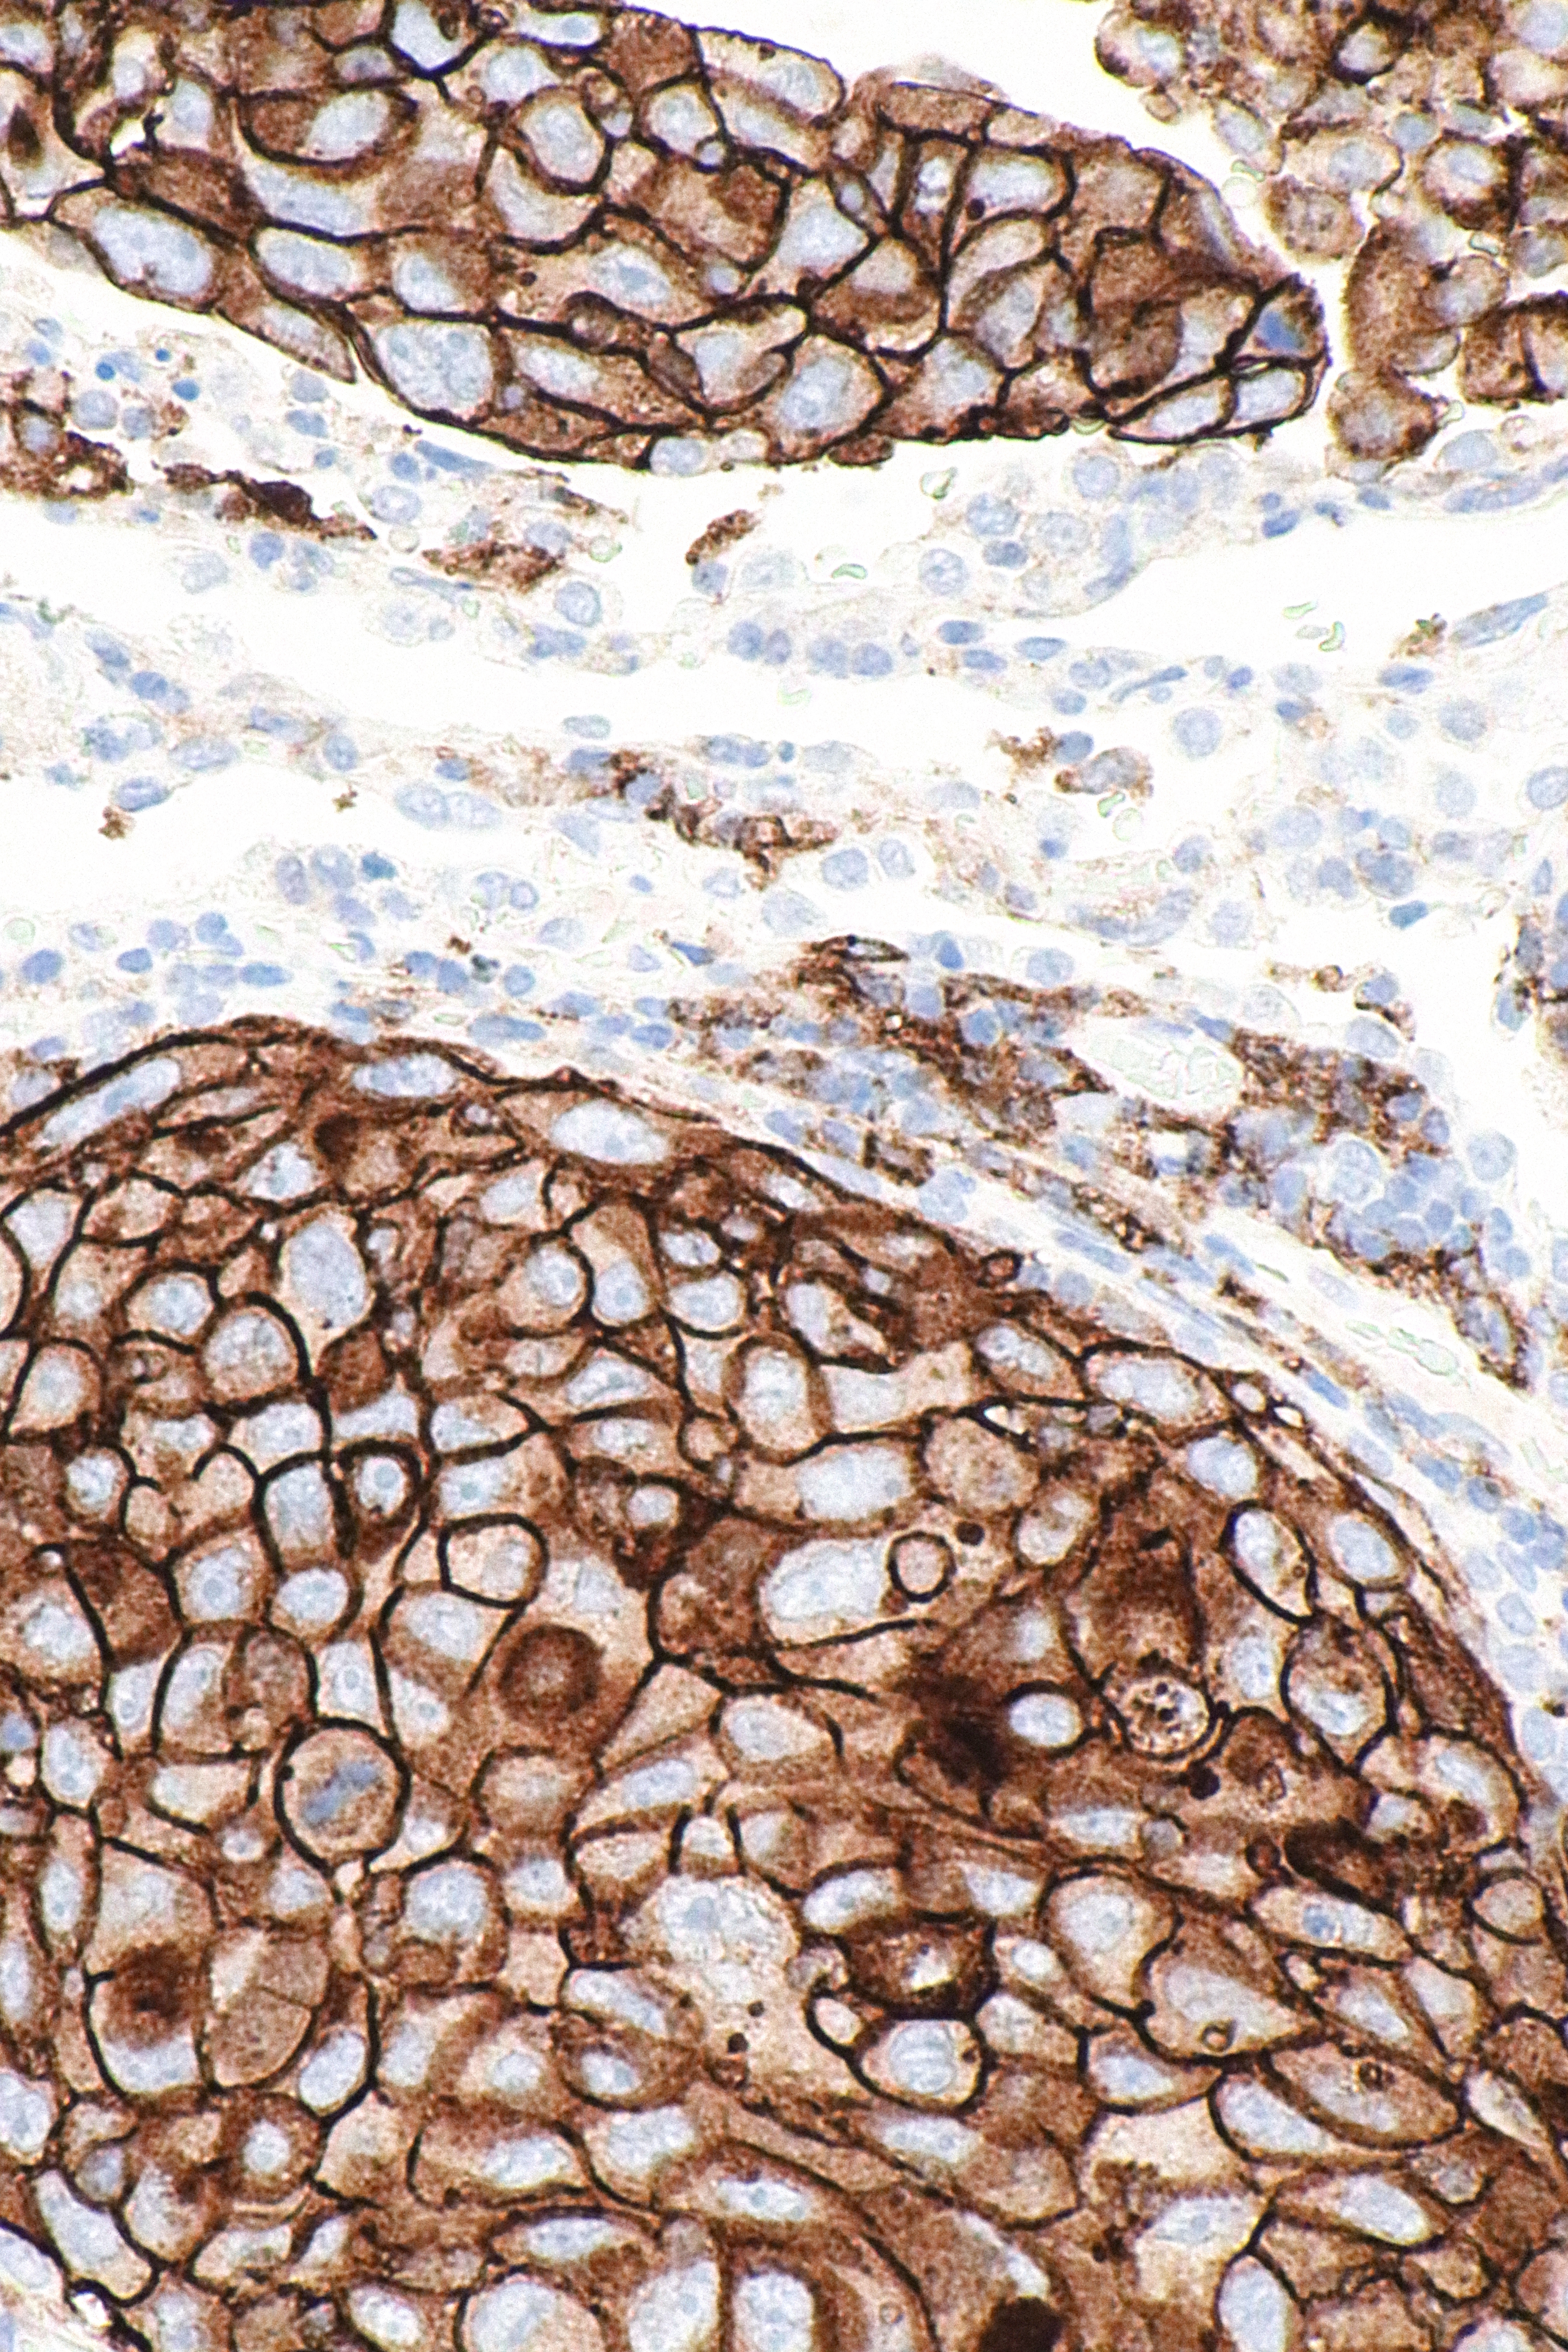

PD-L1은 다양한 악성 종양, 특히 폐암에서 높은 발현을 보이는 것으로 나타났다. PD-1 및 PD-L1 체크포인트를 차단하는 유전자 치료 또는 전신 면역 요법의 효과를 예측하기 위해, PD-L1은 예후 지표이자 항암 면역의 표적으로 사용될 수 있다.[19] PD-L1의 상향 조절은 암이 숙주 면역 체계를 회피하도록 할 수 있다. 예를 들어, 신세포암종 환자 196명의 종양 표본 분석 결과, PD-L1의 높은 종양 발현은 종양의 공격성 증가 및 사망 위험 4.5배 증가와 관련이 있었다.[20]

많은 PD-L1 억제제가 면역 종양학 치료법으로 개발 중이며, 임상 시험에서 좋은 결과를 보이고 있다.[22] 임상적으로 사용 가능한 예로는 두르발루맙, 아테졸리주맙 및 아벨루맙이 있다.[23] 정상 조직에서 STAT3 및 NF-κB와 같은 전사 인자 간의 피드백은 면역 반응을 제한하여 숙주 조직을 보호하고 염증을 제한한다. 암에서는 전사 인자 간의 피드백 제한이 손실되어 국소 PD-L1 발현이 증가할 수 있으며, 이는 PD-L1을 표적으로 하는 약물을 이용한 전신 치료의 효과를 제한할 수 있다.[24] 키메라 항원 수용체 T 세포 (CAR-T)[25] 및 PD-L1을 표적으로 하는 자연 살해 세포 (NK 세포)[26]는 암 치료를 위해 평가되고 있다.

면역 세포(특히 골수성 세포)의 PD-L1 상향 조절은 또한 암 세포의 증식을 가능하게 하는, 매우 국소적인 면역 억제 환경 형성을 초래할 수 있다.[28]

삼중 음성 유방암 (TNBC)에서 PD-L1 분석은 면역 요법 대상 환자를 선택하는 데 필수적이다.

7. 검출 방법

면역 염색을 통해 검출한다.